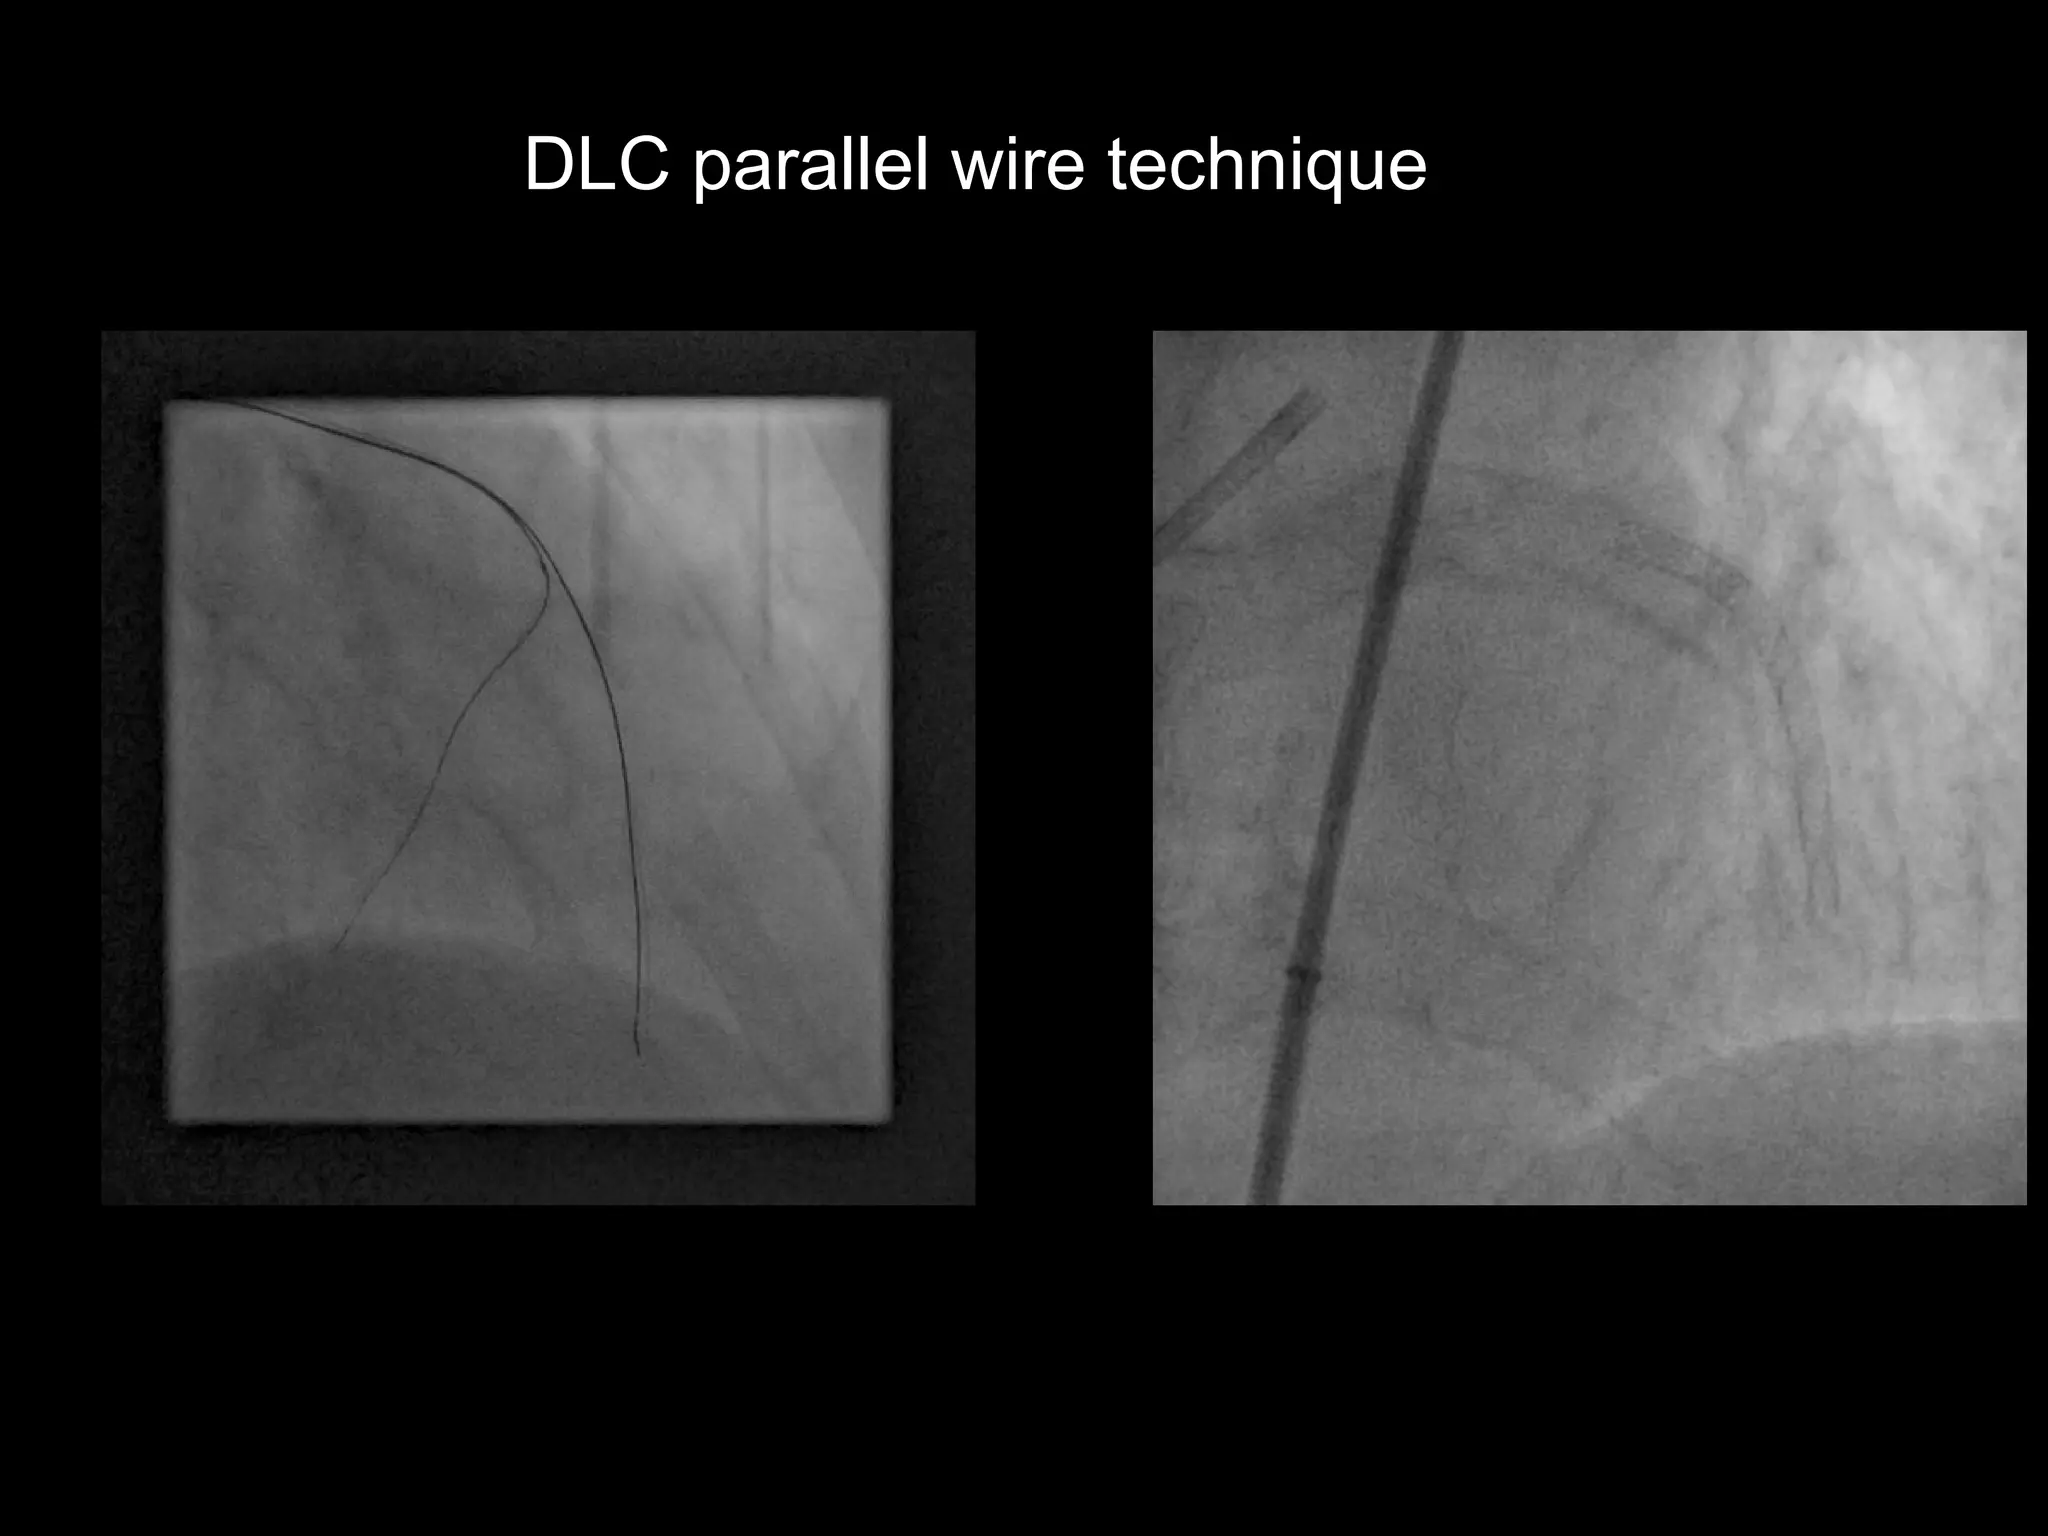

DLC parallel wire technique